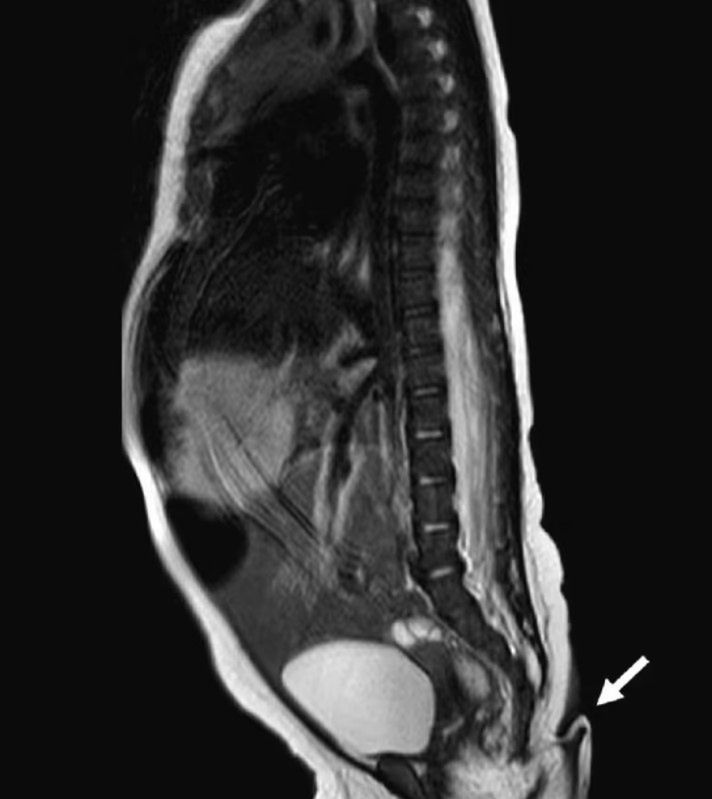

Zaraz po tym, jak lekarze odebrali poród, zauważyli kilkucentymetrowy ogon, który wyrastał w okolicy kości ogonowej, nad pośladkiem dziecka. Zgodnie z raportem czasopisma "Jorunal of Pediatric Surgery Case Reports" ogon miał około 6 cm długości, był miękki, pokryty skórą i cienkimi włosami. Co więcej, ogonem można było swobodnie poruszać, a podczas poruszania nim, noworodek nie odczuwał żadnego bólu.

Do tej pory na całym świecie odnotowano mniej niż 200 przypadków dzieci urodzonych z ogonem. Dr Josue Rueda, jeden z lekarzy, który zajął się dziewczynką po urodzeniu, wyznał, że jest to pierwszy taki przypadek w Meksyku. Co ciekawe, nic nie wskazywało na to, że dziecko urodzi się z ogonem. Lekarze zapewniali, że ciąża kobiety przebiegała prawidłowo, a co więcej, przyszła mama nie była narażona na żadne czynniki, które mogłyby wpłynąć na "rozwój ogona".

Dwa miesiące po narodzinach dziewczynki i jednocześnie po przeprowadzeniu niezbędnych badań, lekarze z Meksyku zdecydowali się na chirurgiczne usunięcia ogona. Odcięta narośl została wówczas poddana analizie. Badania pokazały, że był to ogon, który przypominał ogony występujące u zwierząt.

Dziewczynka urodziła się z 6-centymetrowym ogonem.

Dziewczynka urodziła się z 6-centymetrowym ogonem. © sciencedirect.com

Struktura narośli składała się bowiem z mięśni, naczyń krwionośnych oraz nerwów. Eksperci tłumaczą, że jeżeli płód rozwija się prawidłowo, taka narośl zostaje wchłonięta przez resztę ciała. Naukowcy do tej pory nie wiedzą jednak, dlaczego w niektórych przypadkach ogon nie ulega wchłonięciu.